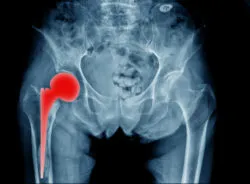

MRI image of hip implantIf you had a hip replacement prior to 2012, you may have been implanted with a device affected by the 2012 Stryker hip implant recall.

The specific devices affected in the Stryker hip implant recall include the ABGII Modular and Rejuvenate Modular Hip Systems.

The cause of the problem? Often the metal-on-metal devices caused corrosion and the release of cobalt and chromium metals into the blood, surrounding tissue, and bone. This condition is called metallosis, a kind of metal poisoning.